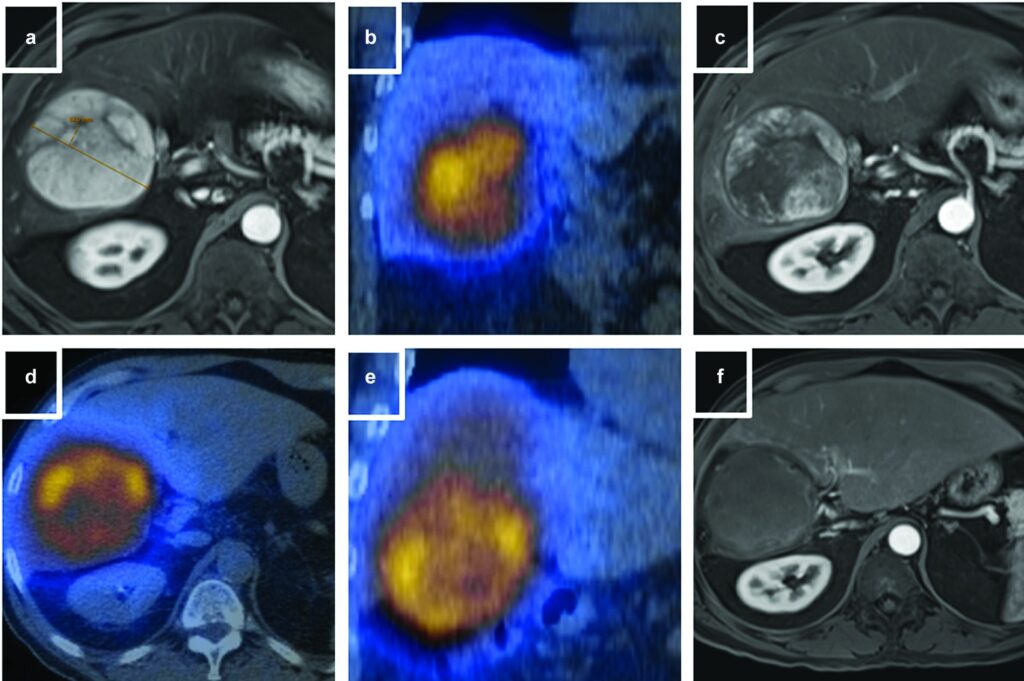

Segmentectomia con radioembolizzazione con ittrio-90 a base di resina (Y90-RE) con dosimetria secondo il Modello MIRD di un uomo di 72 anni con cirrosi da epatite C e un carcinoma epatocellulare (HCC) di 2,8 cm nel segmento 8.

(a) Immagine di Risonanza Magnetica (MRI) con soppressione del grasso in fase arteriosa T1 di una lesione epatica nel segmento 8. La punta di freccia bianca mostra il potenziamento del tumore.

(b) Cateterizzazione sotto-selettiva del ramo dell'arteria epatica che alimenta il tumore. La punta di freccia bianca mostra l'impregnazione (blush) del tumore con il mezzo di contrasto.

(c) Una Cone Beam CT (CBCT) "a secco" ha confermato una buona copertura del tumore al termine della procedura.

(d) La SPECT/CT fusa con tracciante di mappatura di tecnezio-99m macroaggregato (MAA) ha dimostrato un assorbimento soddisfacente nella lesione. Il volume del segmento 8 era di 197 mL. È stata presa la decisione di somministrare 27 mCi con microsfere di resina con 3 giorni di pre-calibrazione per raggiungere una dose di 250 Gy (Gray) all'angiosoma.

(e) Analisi dosimetrica post-trattamento tramite SPECT/CT di Bremsstrahlung di ittrio-90 con contorno del fegato normale (rosa) e contorno del tumore (rosso). La dose effettiva somministrata al tumore è risultata essere 472 Gy; la dose al fegato normale è stata di 37 Gy.

(f) Risonanza Magnetica (MRI) con soppressione del grasso in fase arteriosa T1 a 6 mesi dal trattamento. La punta di freccia bianca mostra una risposta completa nella zona del tumore. Le frecce bianche mostrano i cambiamenti post-trattamento nel parenchima epatico normale circostante.